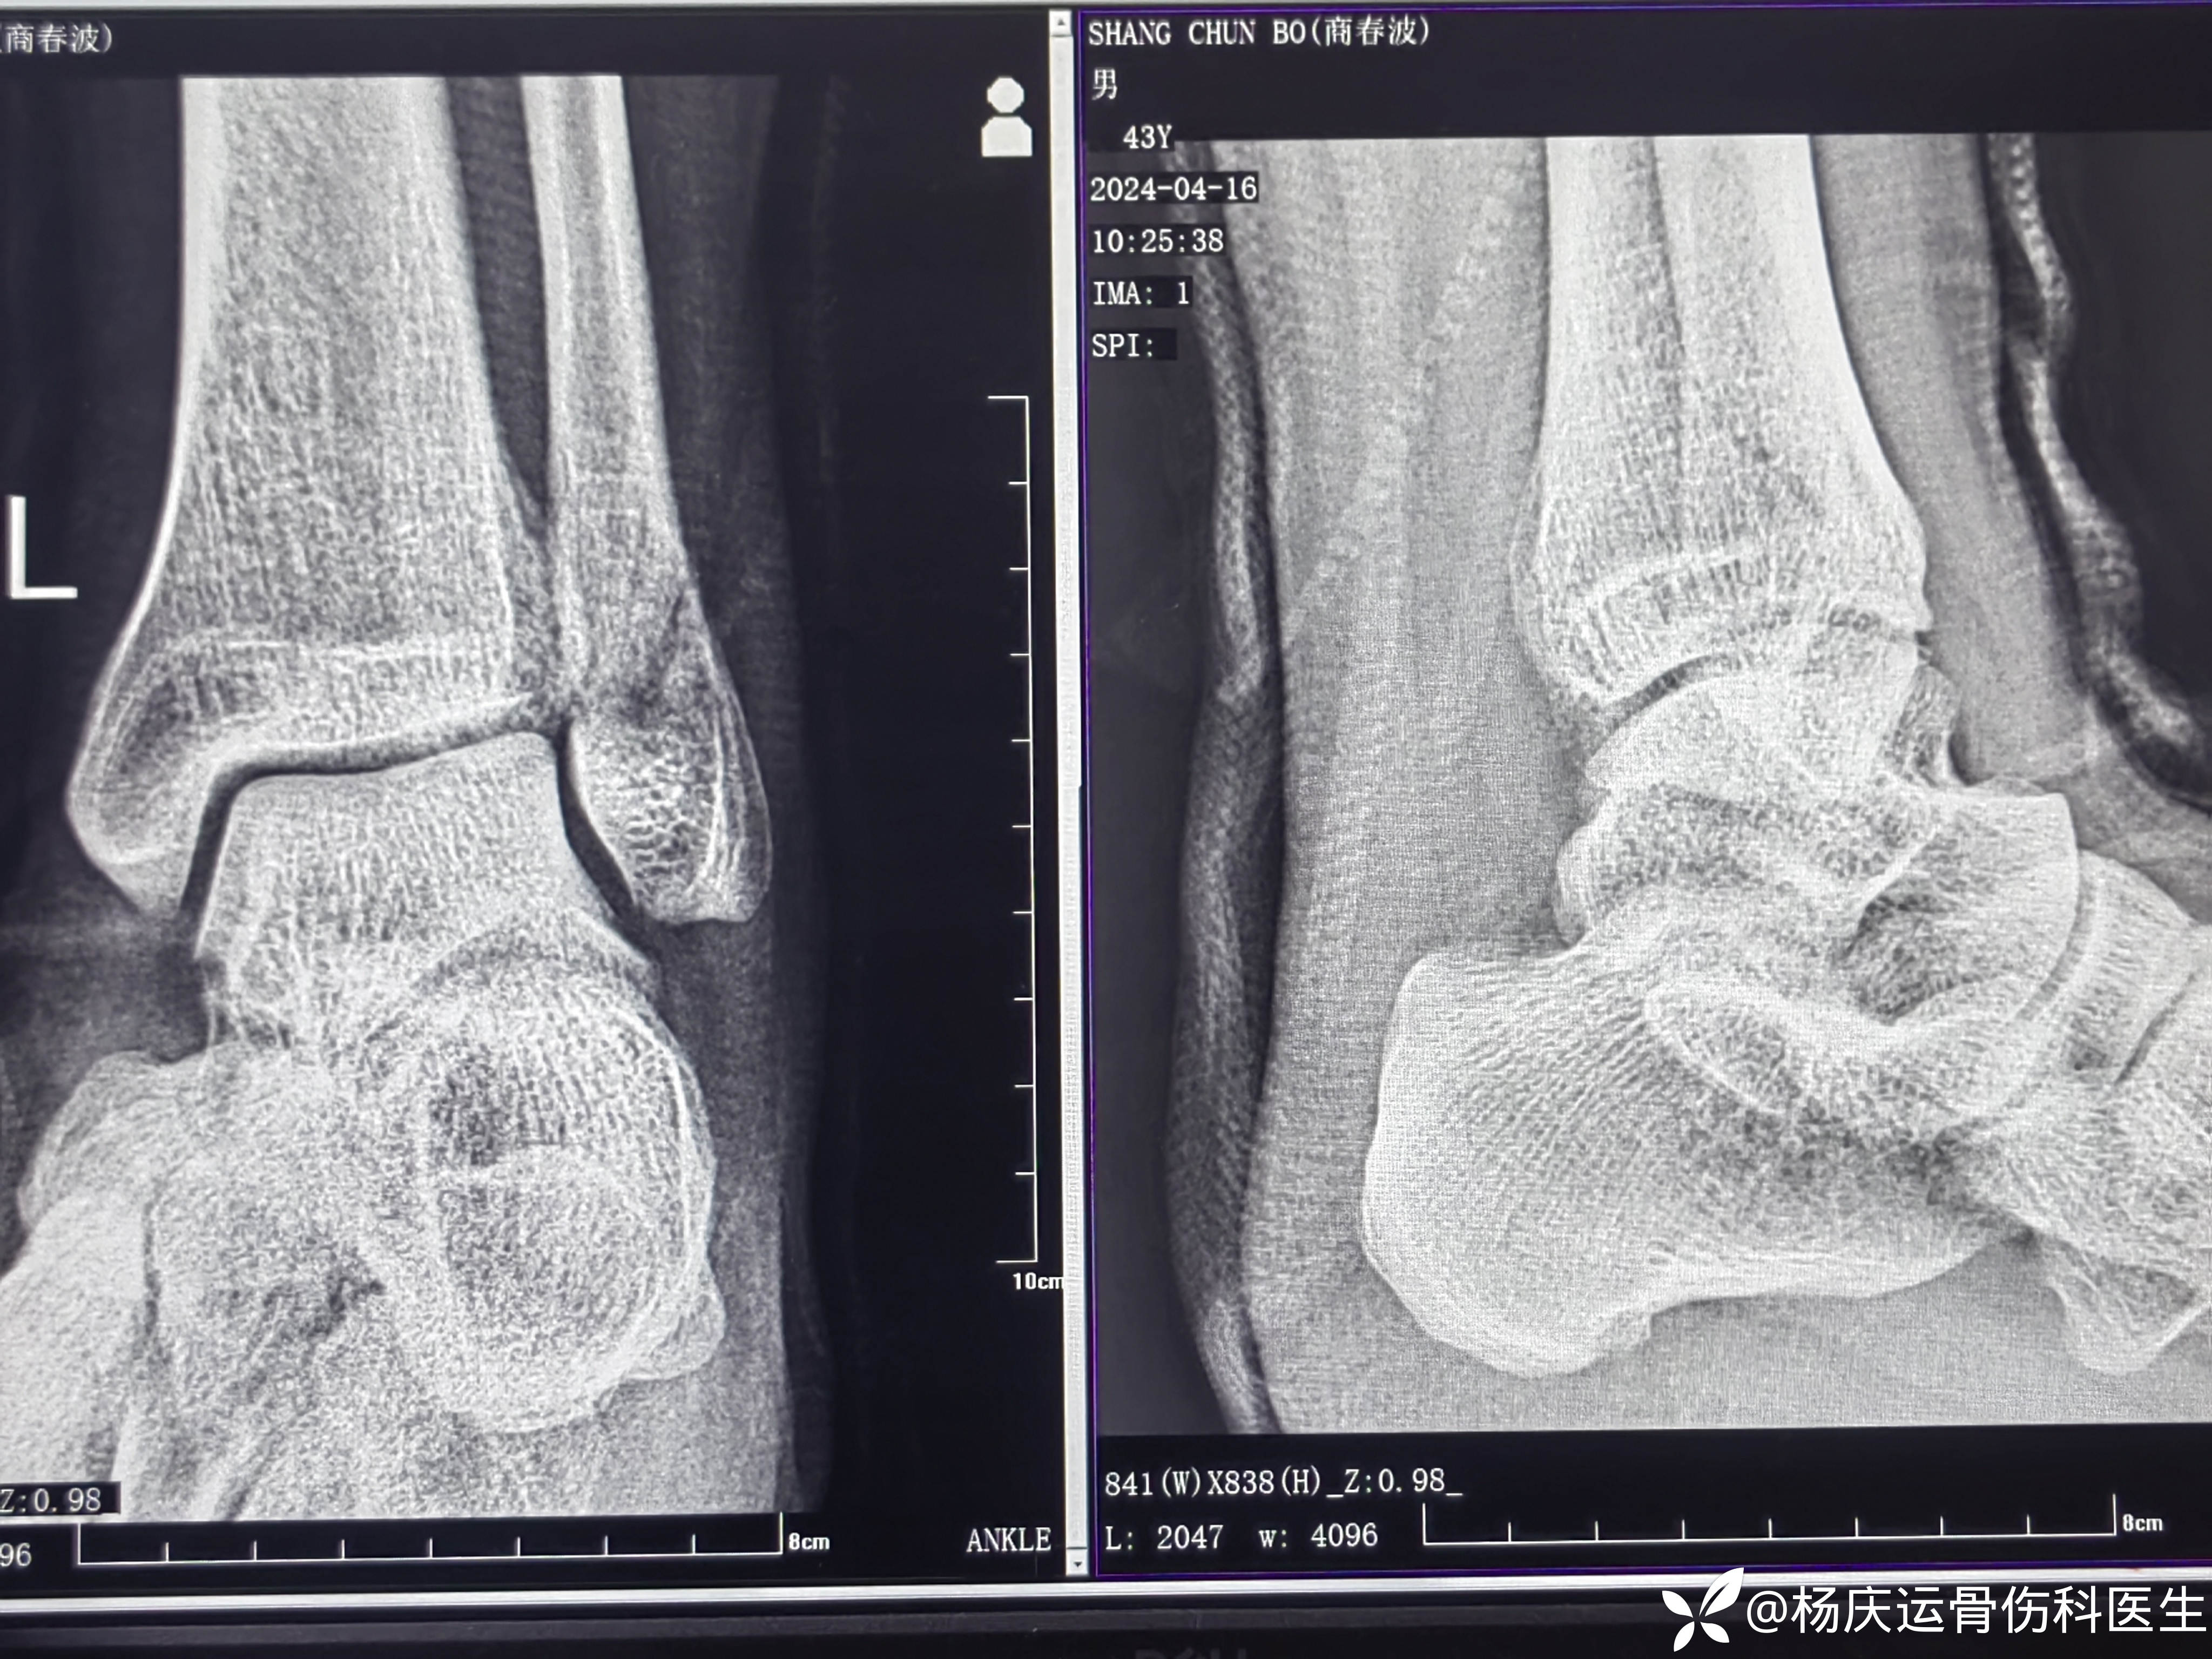

复位前CT